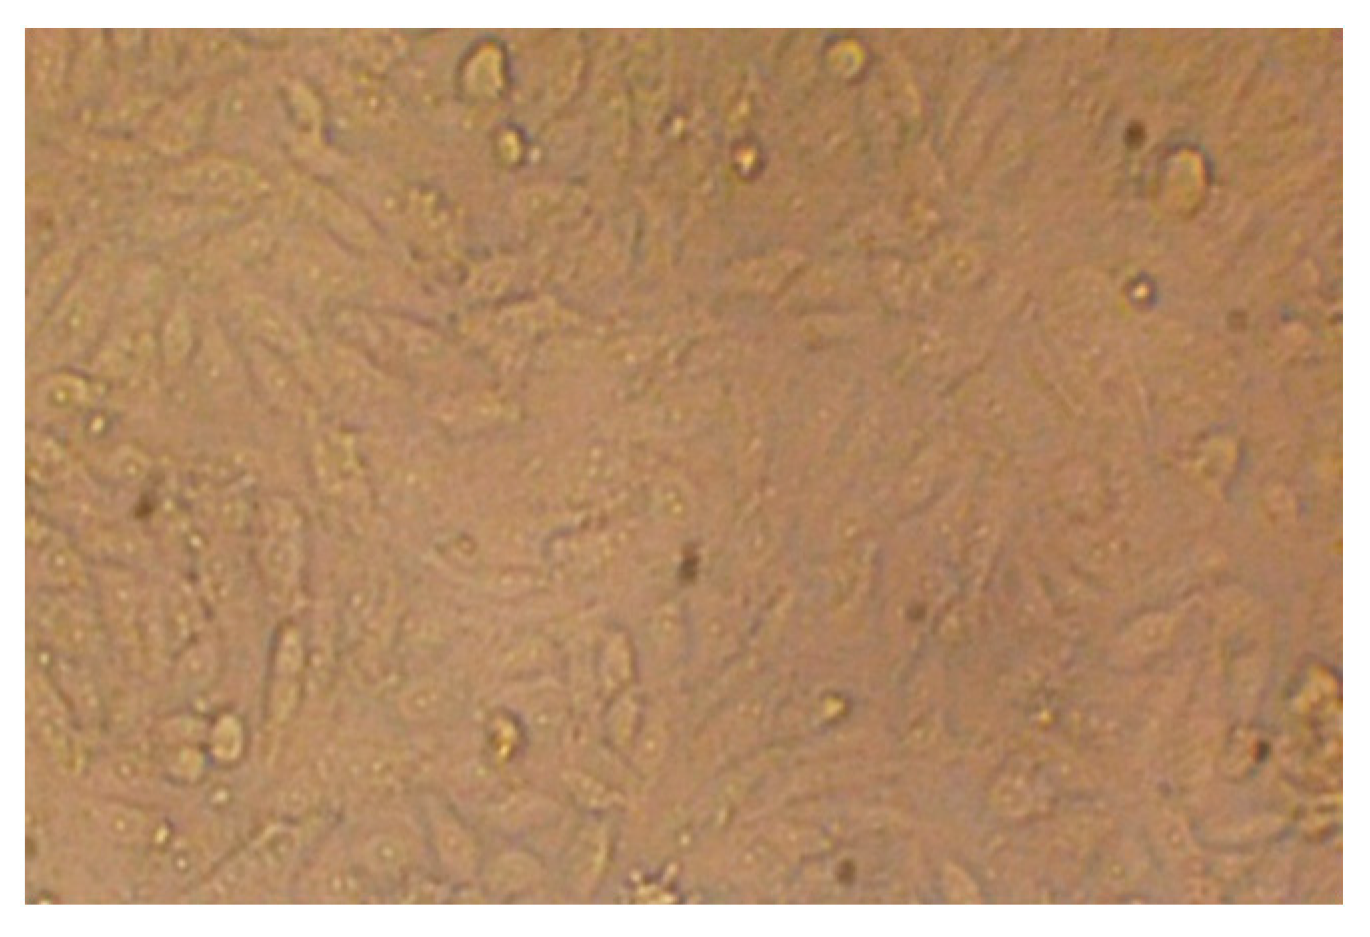

3.8. Cytotoxicity Test